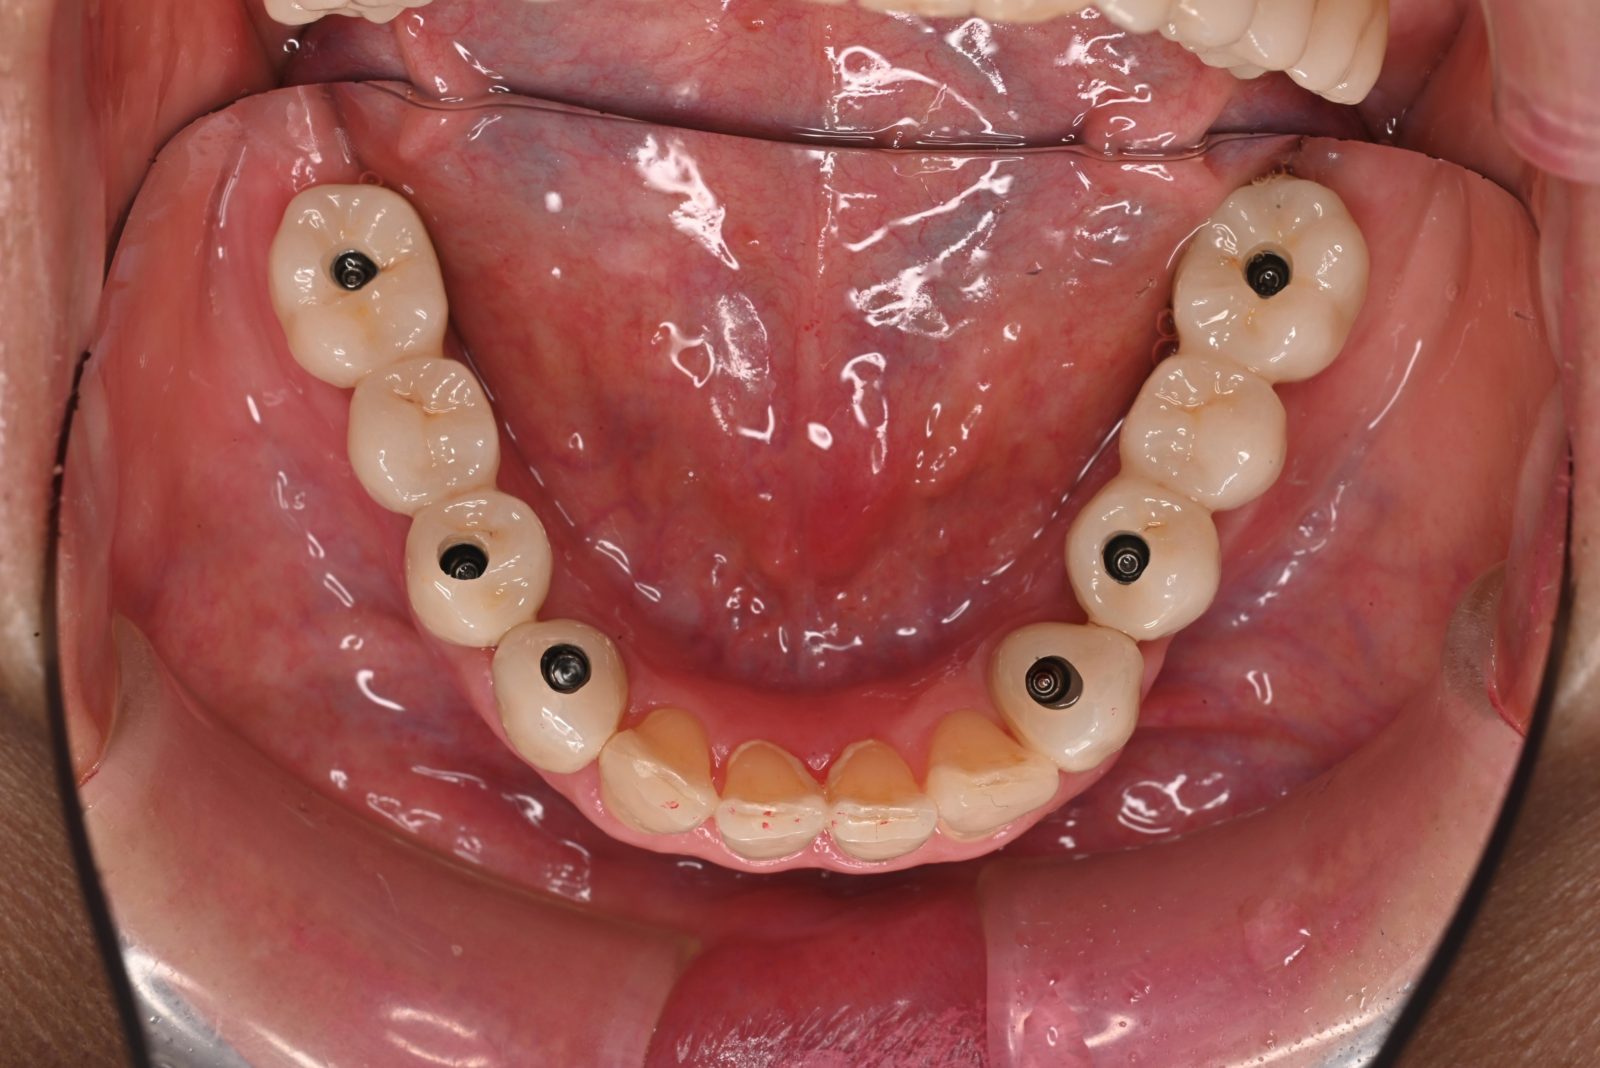

• 治療前

• 治療後

4本のインプラントですべての歯が入るAll-on-4に対応

失った歯の本数だけインプラントを入れようとすると、負担に感じる方が多いのではないでしょうか。そこで行っているのがAll-on-4(オールオンフォー)です。片顎につき最小4本のインプラントですべての歯を支えることができます